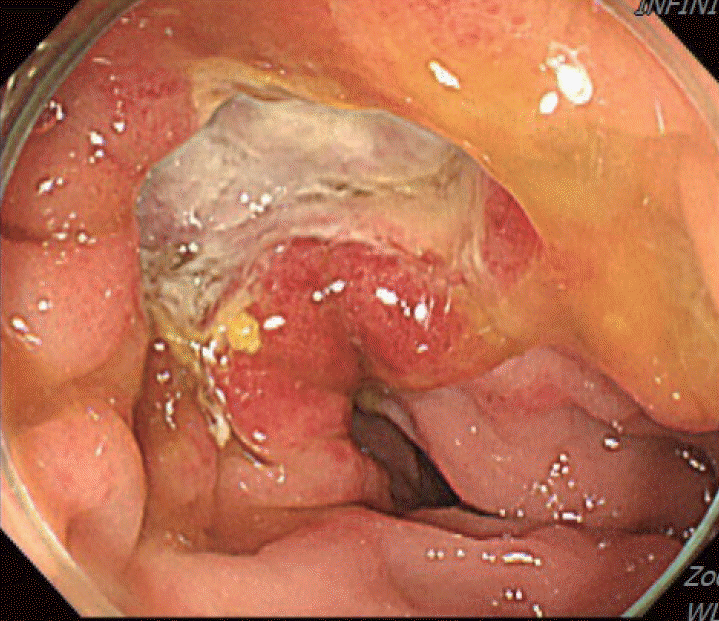

Figure 2.

Initial colonoscopy showing an irregularly shaped gross margin of the ulcer.

A 70-year-old male underwent sigmoidoscopy after a routine computed tomography (CT) examination, which showed thickening of the sigmoid wall (Fig. 1). Sigmoidoscopy revealed a colonic ulcer, and a biopsy was performed. The lesion was identified as a tubular adenoma; therefore, the patient was referred to the gastroenterology department for repeat biopsy and additional tests. The patient’s medical history included high blood pressure and alcoholic hepatitis. His social history showed that he drank 0.5-1.0 bottle of soju daily and was never a smoker. Information regarding his family history was excluded from the study. The patient had no gastrointestinal symptoms such as abdominal pain or diarrhea, and physical examination findings were unremarkable. Although the biopsy showed a tubular adenoma, the initial colonoscopy indicated that the gross margin of the ulcer was irregularly shaped (Fig. 2), raising suspicion for malignancy. Therefore, despite being asymptomatic, the patient was informed, and another colonoscopy was performed 2 months later. The follow-up examination revealed a scarred sigmoid ulcer located 30 cm from the anal verge, which seemed to have improved compared with the previous findings. Re-biopsy demonstrated features consistent with a simple ulcer (Fig. 3). Accordingly, we concluded that this was a benign colonic ulcer with an inflammatory and ischemic cause rather than cancer, and a follow-up CT scan was sche-duled 1 month later. At the follow-up visit 1 month later, the patient complained of abdominal discomfort after eating for a week, which had not occurred before. He denied having fever, chills, nausea, or vomiting. A subsequent abdominal CT scan showed an approximately 9-cm cavitary lesion abutting the sigmoid colon and urinary bladder dome in the small intestine (Fig. 4). This was accompanied by diffuse nodular omentomesenteric infiltration and peritoneal thickening with small ascites. Based on these findings, the patient was suspected to have a malignant tumor, such as scirrhous carcinoma, inflammatory bowel disease, peritoneal carcinomatosis, or peritonitis, and was referred to a surgeon for surgical treatment. The patient was hospitalized immediately. On admission, the patient complained of abdominal discomfort after eating, and mild generalized abdominal tenderness was noted on physical examination. He was hemodynamically stable. Laboratory testing revealed high white blood cell count of 11.45 × 103/μL (normal range, 4.0-10.0 × 103/μL) with a differential of 67.6% neutrophils (normal range, 38.0-75.0), normal hemoglobin of 16.1 g/dL (normal range, 13.0-17.0), normal platelet count of 151 × 103/μL (normal range, 150-400 × 103/μL), and slightly elevated C-reactive protein level of 7.69 mg/L (normal range, 0.0-5.0). Serum electrolyte and kidney function test results were normal. On the 3rd day of hospitalization, the patient underwent laparoscopic small bowel resection. Immunohistochemical analysis of the resected tissue showed positive staining for CD3, CD4, CD8, CD56, and CAM 5.2 (epithelial marker), and a negative staining for CD10, CD20, CD21, and CD30 (Fig. 5). Histopathological evaluation revealed infiltration by small- to medium-sized T-cell with prominent epitheliotropism, consistent with MEITL. The final diagnosis was MEITL, involving the sigmoid colon, urinary bladder, and peritoneum. Postoperatively, the patient developed persistent ileus with progressive ab-dominal distension and loss of bowel passage, necessitating a second emergency surgery on the 20th day of hospitalization. On the 25th day of hospitalization, the Hemovac drainage became purulent, blood pressure decreased, and the patient went into shock; therefore, a third emergency surgery was performed under the suspicion of bowel perforation. On the 45th day of hospitalization, the patient died of refractory septic shock, presumed to be a complication of intestinal perforation.

MEITL manifests as a wide variety of gastrointestinal symptoms, ranging from abdominal pain, weight loss, and diarrhea to serious symptoms such as bleeding, perforation, and obstruction; however, no characteristic clinical symptoms have been established for this disease [6]. Only 10% of affected patients are diagnosed endoscopically, with majority diagnosed through surgery [7]. As in the present case, MEITL is often discovered accidentally without symptoms or is diagnosed when the disease has already progressed [4]. Among few papers presenting the endoscopic findings of MEITL, Tian et al [8]. described this disease as a semicircular shallow ulcer accompanied by numerous fine granules and mucosal thickening. In our patient, ulceration with associated mucosal thickening was also observed. Histomorphologically, neoplastic cells in MEITL are described as small- to medium-sized, monomorphic, and epitheliotropic lymphocytes, with pale cytoplasm and round nuclei [2]. The cells are CD3+, CD4-, CD5-, CD8+, CD56+, CD30-, MATK+, EBER-, and T-cell receptor-gamma delta+ [9]. Cytotoxic markers such as TIA-1, granzyme B, and perforin are also present [9]. Cyclophosphamide-adriamycin-vincristine-prednisone-based chemotherapy, with or without consolidative autologous stem cell transplantation, remains the mainstay of treatment [3]. In an Asian MEITL series, 72% of patients were treated with chemotherapy, whereas 58% underwent both surgery and chemotherapy [5]. However, the high rate of treatment discontinuation owing to disease progression or treatment-related adverse events continues to be a major concern in this patient population [1]. Surgical resection is necessary when symptoms appear, and approximately 50% of patients undergo emergency surgery for intestinal perforation or obstruction [5,7]. If intestinal perforation occurs, the prognosis is expected to be worse, as chemotherapy is delayed owing to peritonitis, septic shock, and multiple organ failure [10]. In the present case, treatment was likely delayed because of intestinal obstruction prior to anticancer therapy, leading to rapid clinical deterioration. Generally, the diagnostic ratio of intestinal T-cell lymphoma (ITCL) by endoscopy, including tissue biopsy, is low [11] for the following reasons: 1) tissue specimens from endoscopic biopsy are usually not sufficiently large to allow a correct diagnosis; 2) ITCL is primarily located in the submucosa and smooth muscle, and detection of the lesion through the mucosal layer from biopsy specimens is difficult; and 3) the disease can easily be overlooked because of its rarity. Therefore, tissue biopsies of ulcerative gastrointestinal lesions should be performed carefully from the base of the ulcer while considering the possibility of malignant lymphoma [11]. In this patient, despite a prompt biopsy following the incidental detection of a colonic ulcer and a second endoscopic biopsy performed shortly thereafter, an endoscopic diagnosis could not be achieved. If several deeper biopsies, including those of the submucosa, were performed at the time of the initial endoscopy, the possibility of early diagnosis may have increased. Moreover, although our patient underwent colonoscopy over a short follow-up period, the ulcer showed an atypical clinical course, appearing to improve and form a scar within a short interval. Such a presentation has rarely been reported in the related literature, and we report this case to highlight its unusual endoscopic features. Additionally, owing to this atypical pattern, careful differen-tiation from other diseases, such as benign ulcers or inflammatory bowel disease, is necessary. Our case underscores the importance of early diagnosis of MEITL, as the rapid progression of the disease can have a fatal consequence. Endoscopists and clinicians need to be vigilant in understanding endoscopic and histological findings to ensure prompt diagnosis and treatment of this aggressive disease.